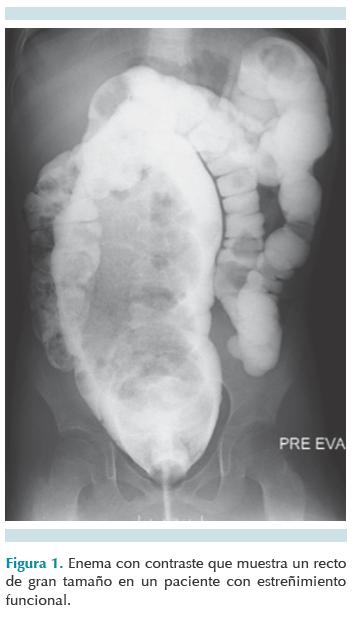

En el estreñimiento funcional, también conocido como estreñimiento primario, el principal detonador para la retención fecal es la evacuación dolorosa, la que lleva a mayor retención con la finalidad de evitar el dolor; en breve, la pared rectal se acomoda al nuevo contenido y la sensación de evacuar se pierde hasta que llegan más heces al recto, distendiendo nuevamente sus paredes y vuelven a desencadenar la sensación para evacuar. La retención fecal va distendiendo de manera progresiva el recto, el cual aumenta su diámetro (megarrecto) (Figura 1) y disminuye la elasticidad de la fibra muscular. 3-5

El colon por enema se indica en pacientes con datos clínicos sugestivos de malformaciones anatómicas, estenosis colónica o enfermedad de Hirschsprung.6-9

La forma de realizar el enema con contraste es utilizando una sonda sin globo y colocando cinta adhesiva en cantidad suficiente para crear un tope a 1 cm del orifico distal de la sonda para evitar fuga del medio de contraste. La sonda se introduce máximo 1 cm y se utiliza contraste hidrosoluble sin bario; se instila el medio con jeringa de irrigación lentamente y sin ejercer mucha presión; se utiliza el fluoroscopio para tener una visualización dinámica que permita hacer una mejor evaluación. El estudio siempre lo iniciamos en proyección lateral. Ante la sospecha de enfermedad de Hirschsprung el estudio debe realizarse sin preparación intestinal previa, evitando la manipulación rectal 48 horas antes y con la menor cantidad posible de contraste, así como introducir lo menos posible la sonda para evitar que por esta razón no se determine la zona de transición.8